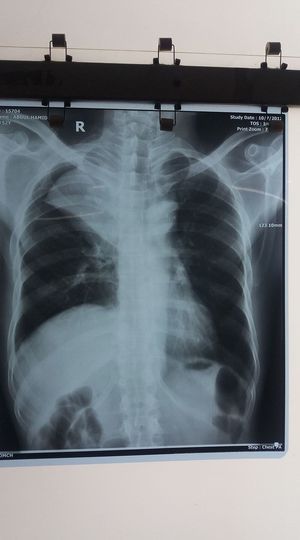

Diagnosis pals????

Pneumonia of the right lung upper lobe

Yes but also with a collapse